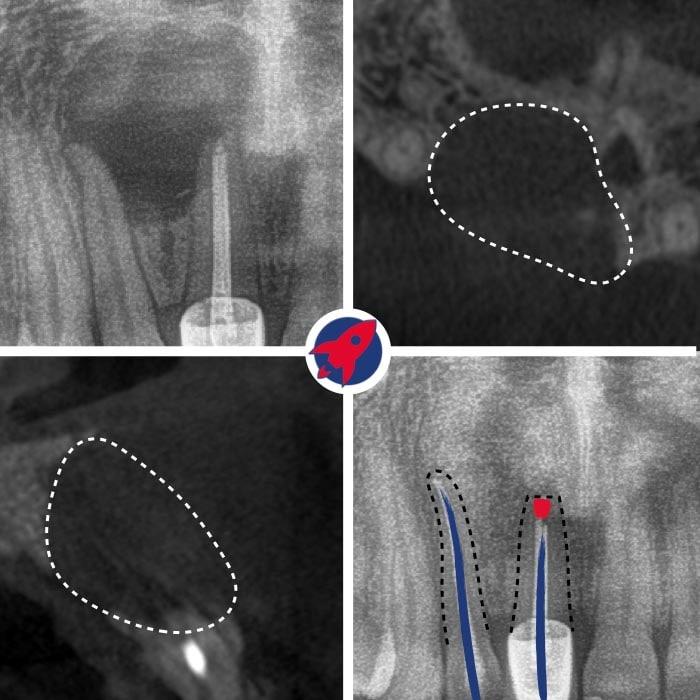

Treatment Under the Dental Microscope

The core of our endodontics. The up to 25x magnification enables the visualization of the finest canals, which are impossible to find with the naked eye.

Cleaning Under the Microscope

The tooth is isolated. Using the X-ray and the magnification of the microscope, the canals are opened, flushed, and cleaned and disinfected with machine-driven instruments down to the tip.